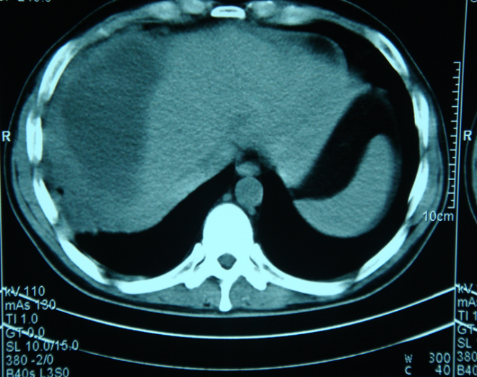

- Diaqnozu dəqiqləşdirmək üçün Qc venaları yoxlanılmalıdır. Bunun üçün dopler USM, KT-angioqrafiya, MRT-angioqrafiyalar və ya kontrastlı venoqrafiya edilir.

- Görüntüləmədə Qc venalarının trombotik tutulması diaqnozu dəqiqləşdirən əlamətdir.

PVT diaqnozunu dəqiqləşdirmək üçün portoqrafiya aparılır – Doppler USM, KT və ya MRT angioqrafiya.

- Kontrastlı müayinələrdə damarda tromb və ya kavernoz transformasiya

Qaraciyər venalarının görünməməsi, kontrastlaşmaması və ya trombla tıxanması.